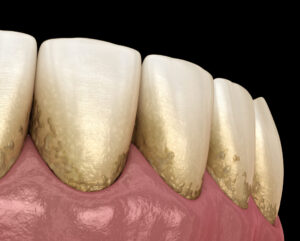

・歯垢や歯石

・歯石や歯垢の付着状態

歯周病が関係している口臭では、歯周ポケットの中や歯の根元に、細菌のすみかとなる汚れがたまりやすくなります。

これらの汚れは、毎日の歯磨きだけでは取り除くことが難しい場合があります。

・歯ブラシでは落としきれない歯石や歯垢の除去